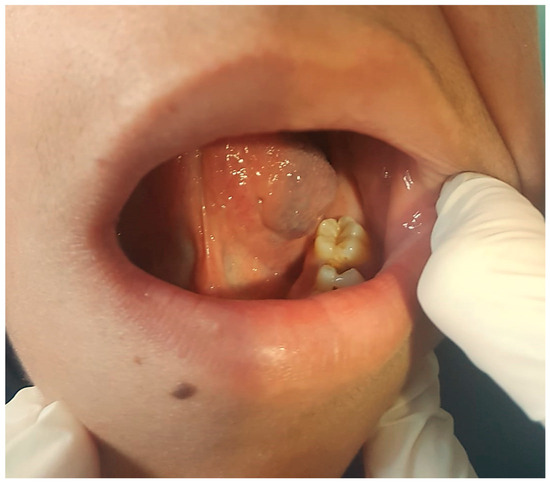

3.2. Lymphatic Malformations

3.2.1. Clinical Data

3.2.2. Diagnosis

3.2.3. Therapy